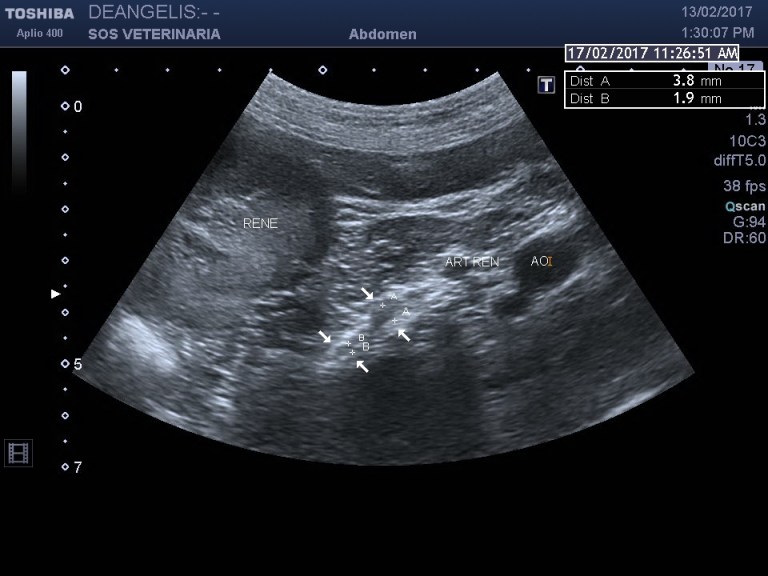

Esame ecografico eseguito dopo 4 mesi dalla diagnosi

la riduzione del volume ghiandolare e’ impressionante ,non si visualizza piu’ la surrenale un attenta valutazione la individua con diametri di appena 1,9 al polo craniale e 3,8 al polo caudale (atrofia post necrosi)